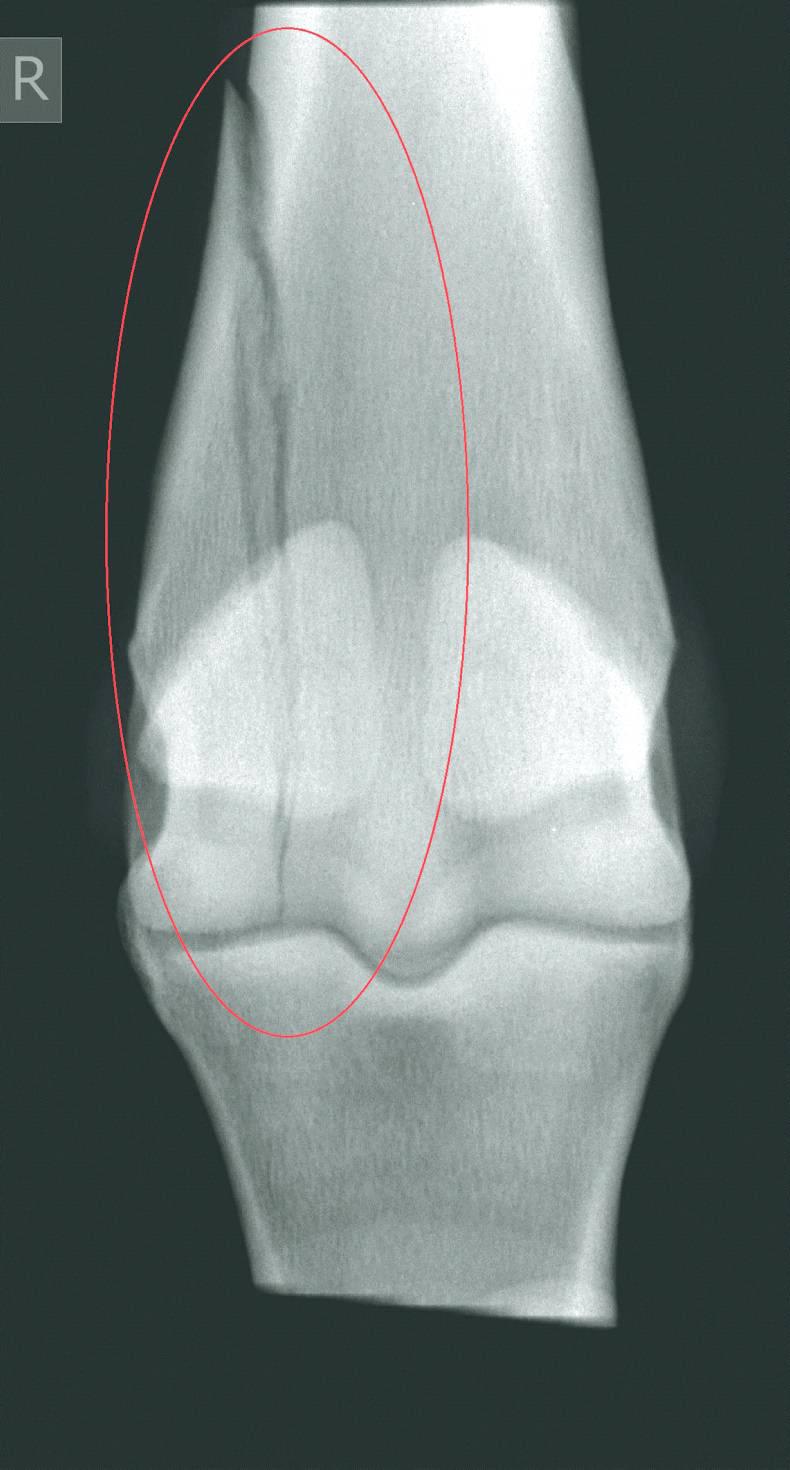

CONDYLAR fractures refer to fractures of the lower part of the cannon bone. The medial and lateral condyles are rounded prominences of the lower cannon bone which articulate with the long pastern bone forming the fetlock joint.

They are the most common fracture seen in the long bones of racehorses. Condylar fractures are twice as likely to occur in forelimbs and four times more likely to occur in the lateral condyle compared with the medial condyle.